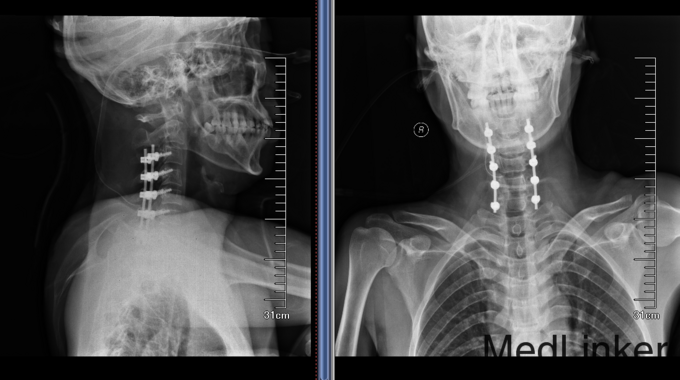

诊断:颈椎外伤(不全瘫);脊髓损伤 患者入院后完善相关检查,查无手术禁忌症后急诊行颈椎后路椎板减压椎管扩大单开门侧块螺钉内固定术,术后患者生命体征平稳,双上肢感觉疼痛,双下肢足趾肌力恢复到1级,术后3天后转入康复科继续康复治疗。